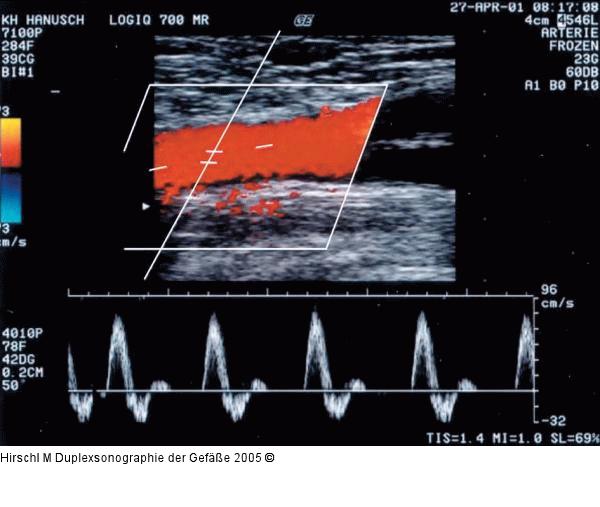

Abbildung 14: Duplexsonographie - Pulsdoppler Gut eingestellter Pulsdoppler, triphasisches Signal im Bereich einer A. fem. com. knapp vor der Femoralisgabel. Nicht optimal eingestellt sind Meßvolumen (zu sehr zentriert) und Farbgain (Farbe auch außerhalb des Gefäßes). |

Gut eingestellter Pulsdoppler, triphasisches Signal im Bereich einer A. fem. com. knapp vor der Femoralisgabel. Nicht optimal eingestellt sind Meßvolumen (zu sehr zentriert) und Farbgain (Farbe auch außerhalb des Gefäßes). |